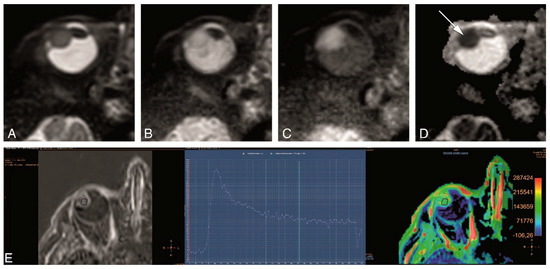

4.3. Functional MRI of Uveal Melanoma